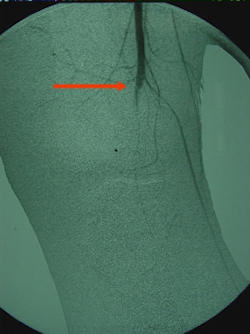

Popiteal arter, orta hattın lateralinde, tibiaya 4-9 mm mesafededir. Postero-lateral köşe yaralanması sonrasında, arterde laserasyon, tromboz, A-V fistül, yalancı anevrizma gibi lezyonlar oluşabilir. İntimal hasar sonrası geç tromboza dikkat edilmelidir. Damar yaralanmalarının insidansı % 4 –35 arasında bildirilmiştir. Şüpheli durum varsa anjiyogram yardımcıdır, şüphe yok ise doğrudan cerrahi yapılmalıdır, zira hasarın nerede olduğu bellidir. Anjiyogram ile vakit kaybedilmesi uygun olmaz, zira 6 saat içinde dolaşım sağlanmaz ise % 68 oranında amputasyon bildirilmiştir.